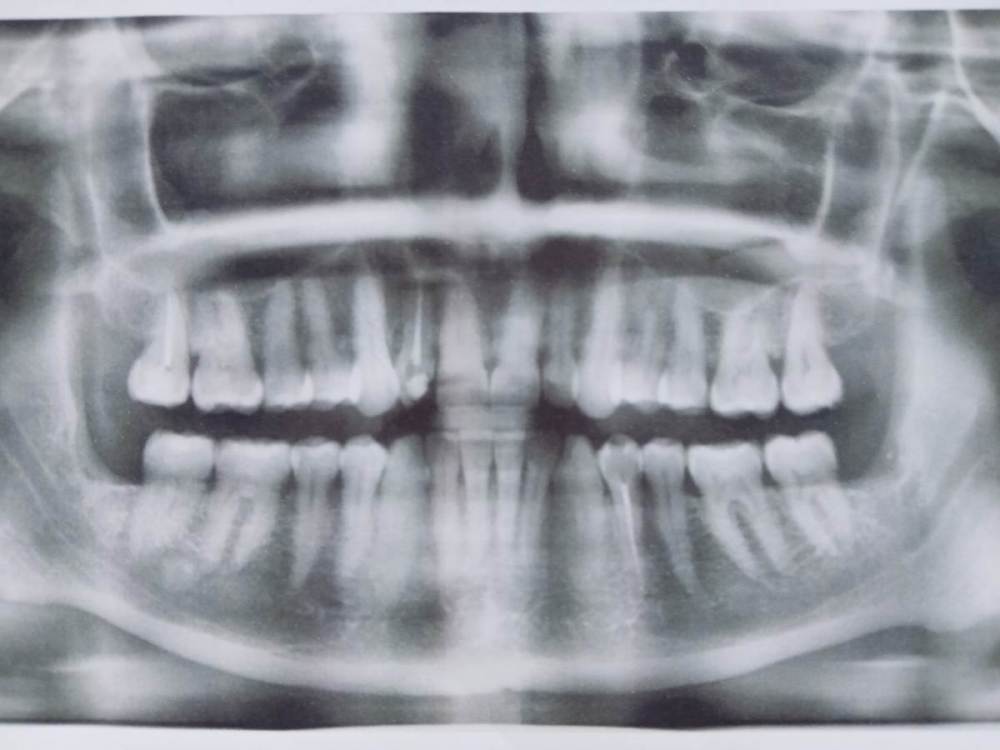

annda Опубликовано 25 июля, 2023 Поделиться Опубликовано 25 июля, 2023 Могут такие боли и такие симптомы давать мышцы.Вы-бруксист со стажем и ваша панорама красноречиво об этом говорит Вам надо научиться контролировать свои мышцы хотя бы днем.Следите,чтобы зубы всегда были в разомкнутом состоянии,чем бы вы не занимались.Найдитюе комплексы упражнений для расслабления мышц лица,шем ,воротниковой зоны и далее вниз.качайте приложение "Brux up" и следите за собой с его помощью до улучшения состояния.Можете и потом им пользоваться. Ссылка на комментарий

annda Опубликовано 27 июля, 2023 Поделиться Опубликовано 27 июля, 2023 (изменено) Нельзя на ортодонтию идти в таком состоянии. Начните с банальной рутинной ежедневной самокоррекции хотя бы-пилатес,йога, Фельденкрайз и прочие подобные штуки. Единственные рубцы,которые у вас есть-это «линия Альба»,,следы прикусывания щек зубами.К месту удаления это не имеет никакого отношения, а к бруксизму -самое прямое. Изменено 27 июля, 2023 пользователем annda Ссылка на комментарий